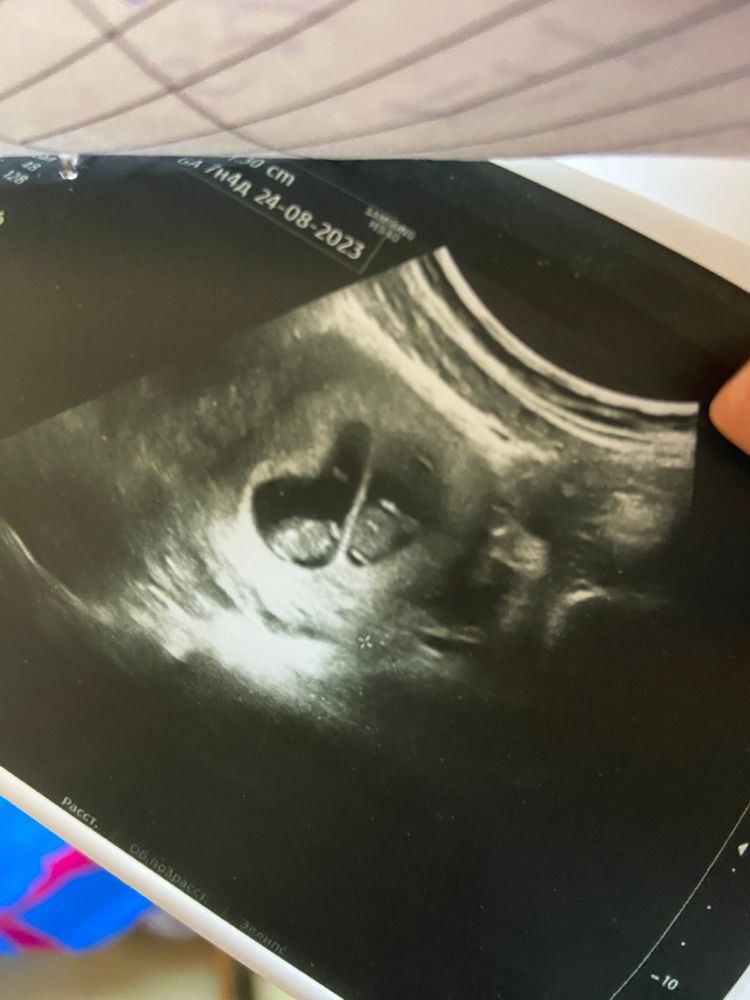

9ая неделя🥰